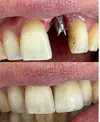

Zirkonyum uygulamalar

Implant tedavisi

Porselen uygulamaları